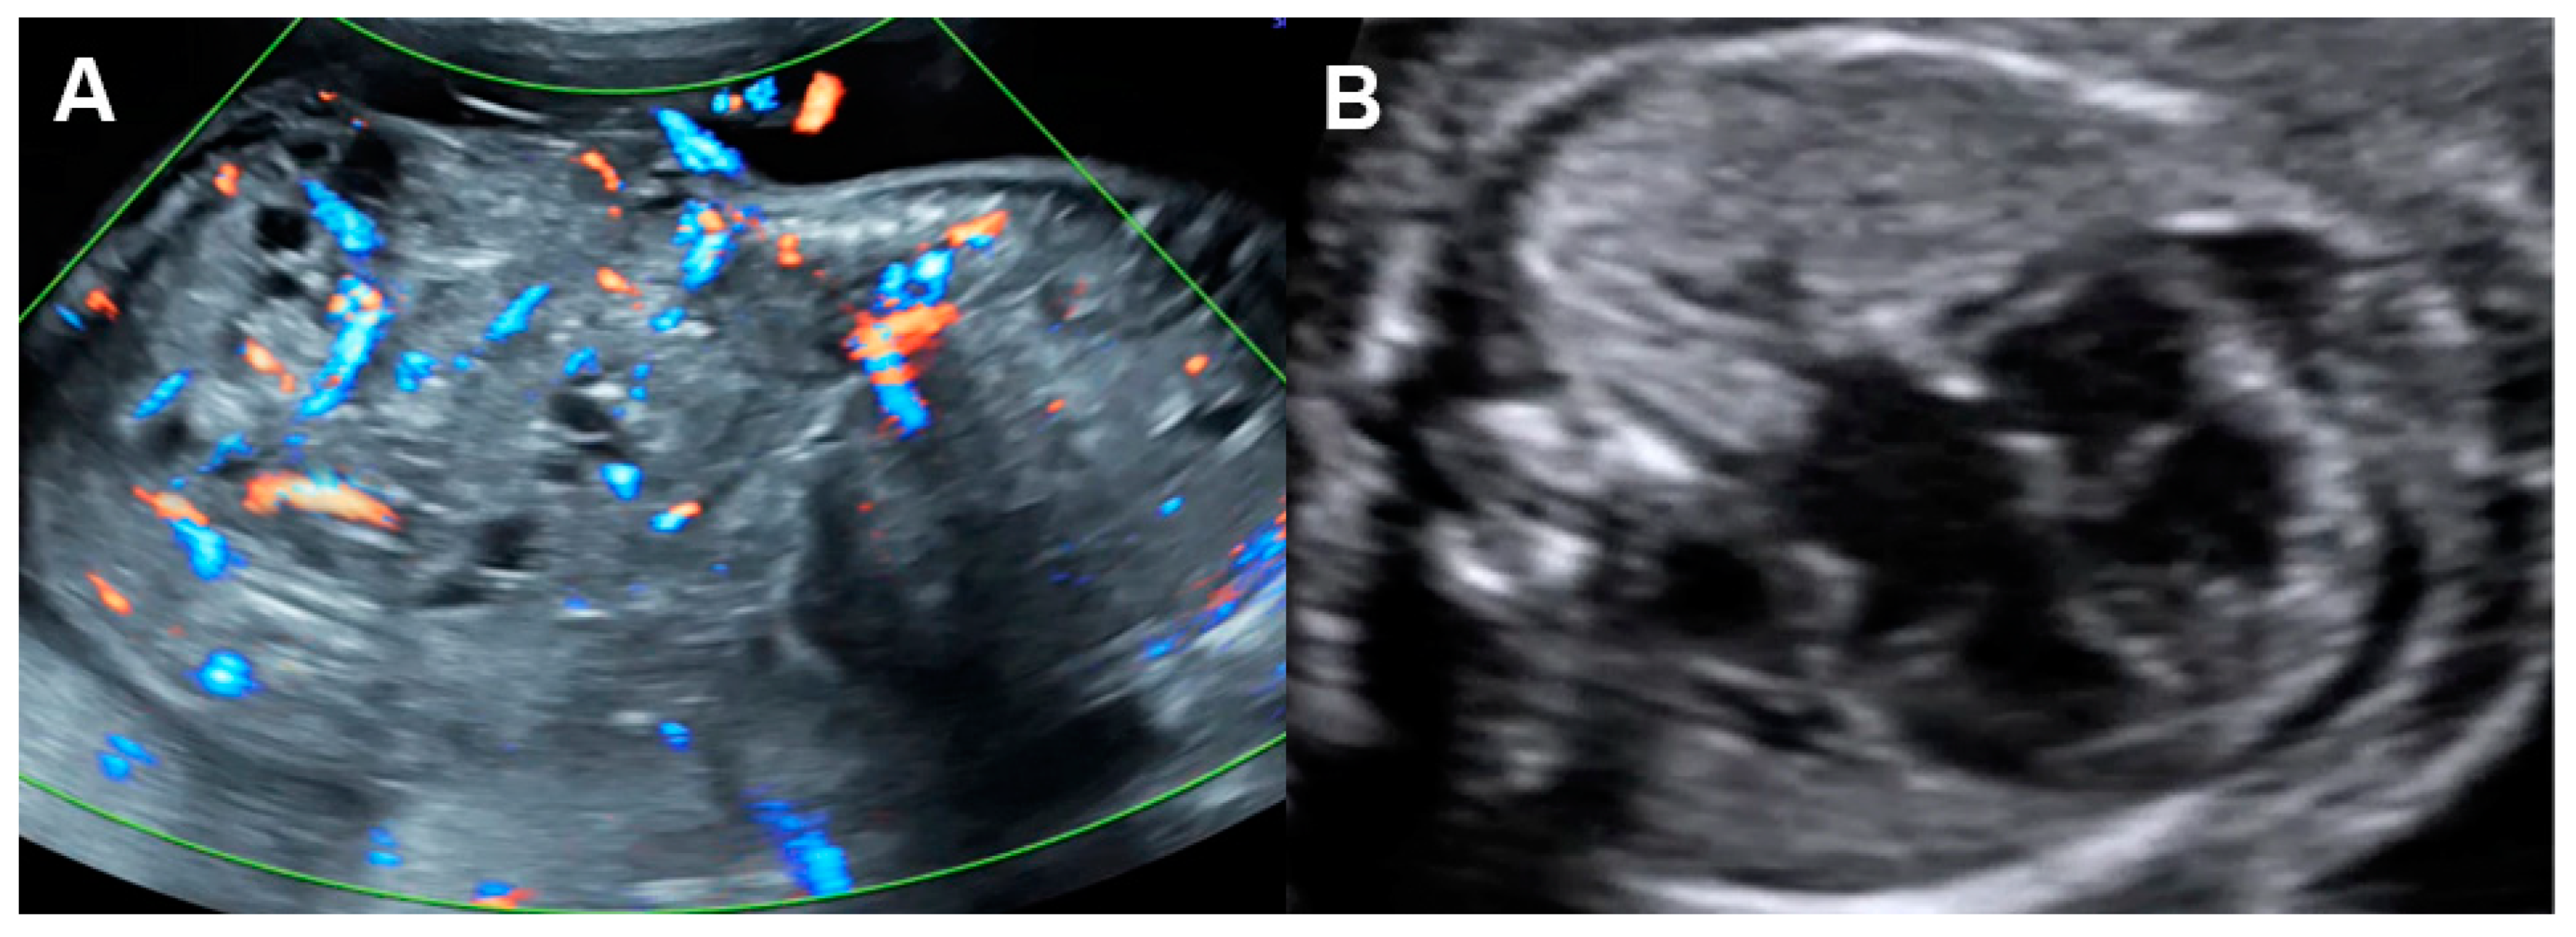

5.7. Ductal Arteriosus Constriction

- Mori, Y.; Rice, M.J.; McDonald, R.W.; Reller, M.D.; Wanitkun, S.; Harada, K.; Sahn, D.J. Evaluation of systolic and diastolic ventricular performance of the right ventricle in fetuses with ductal constriction using the Doppler Tei index. Am. J. Cardiol. 2001, 88, 1173–1178. [Google Scholar] [CrossRef]